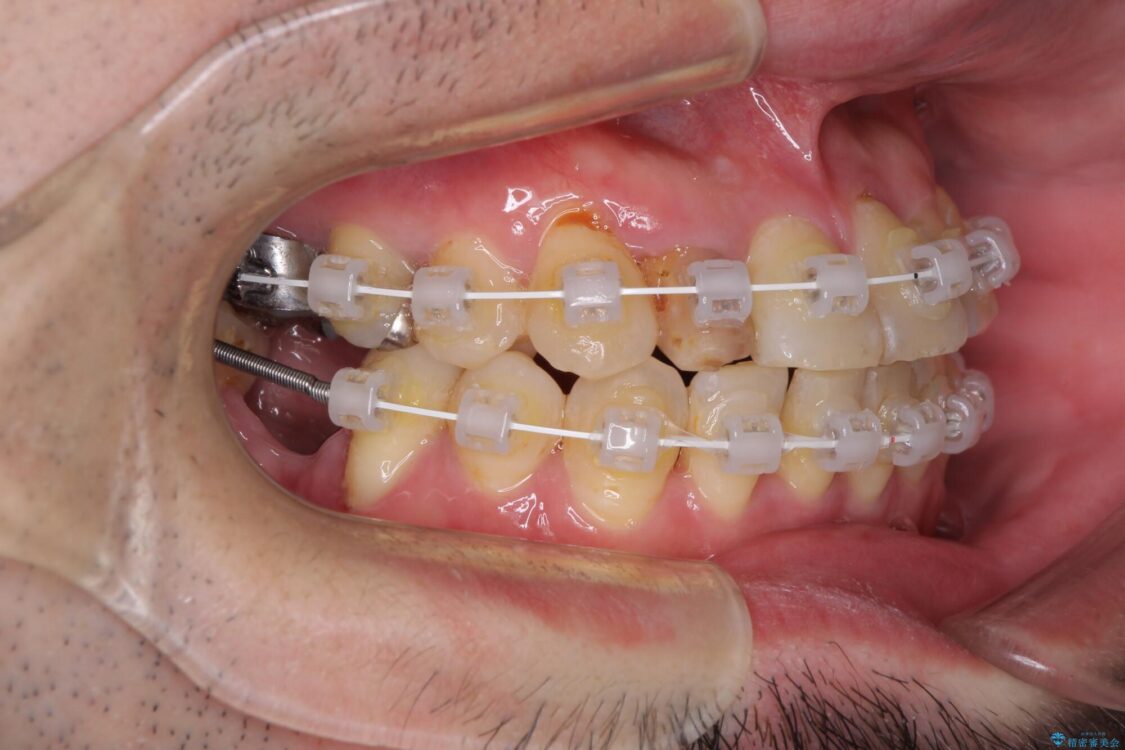

治療途中

咬み合わせは受け口傾向であり、上顎前歯の叢生が顕著であったことから、第1小臼歯抜歯による矯正治療も検討しましたが、下顎大臼歯を左右ともに抜歯するため、非抜歯による矯正治療を行うこととしました。

矯正治療でインプラント埋入を行い、矯正治療後に気になる前歯と合わせてオールセラミッククラウンによる補綴治療を行うこととしました。